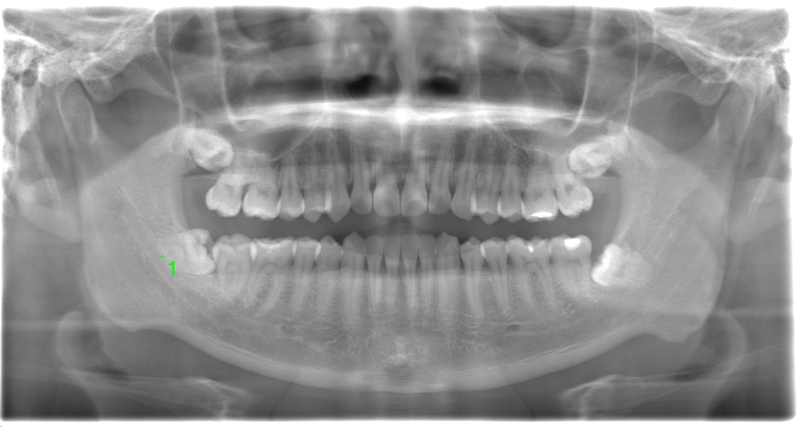

CASE 4

基本情報

| 年齢・性別 | 30代・男性 |

| 主訴 | 左上親知らず抜きたい |

| 抜歯期間 | 15分 |

| 抜歯費用 | 約2,000円(保険内) 別途CT撮影で3,000円 |

| 抜歯内容 | 左上の親知らず抜歯 |